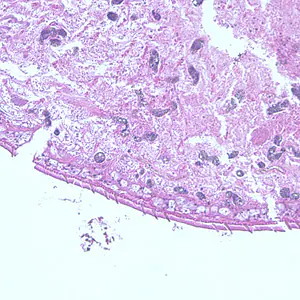

Eggs of Paragonimus spp. in tissue.

Diagnosis is based on microscopic demonstration of eggs in stool or sputum, but these are not present until 2 to 3 months after infection. (Eggs are also occasionally encountered in effusion fluid or biopsy material.) Concentration techniques may be necessary in patients with light infections. Biopsy may allow diagnostic confirmation and species identification when an adult or developing fluke is recovered.